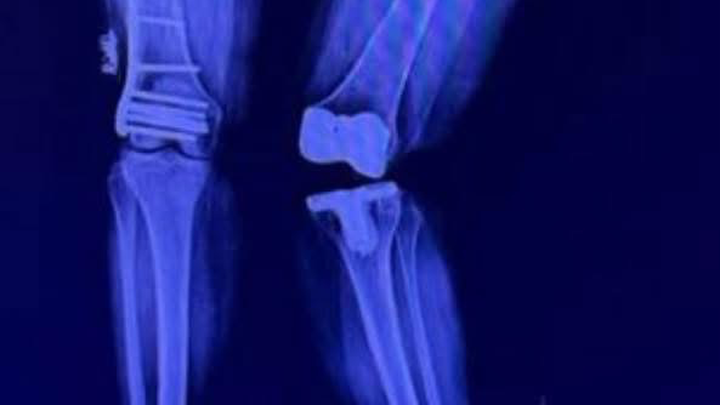

My name is “Suzy” Britz, I’ve spent my life helping others heal, rescuing animals, and as a Texas Realtor, guiding families and investors to build wealth. Now, I find myself on the other side, in urgent need of support. After a sudden fracture on August 13th left my tibia broken in half, I’ve been unable to walk or work. This injury, along with past orthopedic conditions and a misaligned knee replacement, has left me facing multiple surgeries and months of rehabilitation.

My savings are gone, and emergency SSDI does not cover my rent, medical care, or the accessibility modifications I need to recover safely. I urgently need help with housing, utilities, medical co-pays, physical therapy, transportation, and accessibility equipment. I am currently in therapy twice a week to gain enough strength for two critical surgeries: a total left knee replacement and a revision to a hinged knee replacement.